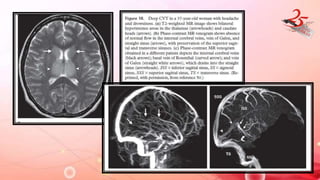

DEEP CVT

IMAGING FINDINGS:

• Superficial CVT: cerebral edema and venous infraction of cerebral

cortex near vertex.

• Deep CVT: Venous HTN , b/L involvement of thalamus and basal

ganglia.

• MRI/CT: Venous HTN and cerebral edema results in T2

hyperintensity in thalamus , BG , internal capsule and DWM

• Hemorhhagic transformation common

• MR venogram : evaluation of thrombus

DEEP CVT • CAUSE: hypercoagulable states , OCPS , vasculitis , intracranial / systemic infections IMAGING FINDINGS: • Superficial CVT: cerebral edema and venous infraction of cerebral cortex near vertex. • Deep CVT: Venous HTN , b/L involvement of thalamus and basal ganglia. • MRI/CT: Venous HTN and cerebral edema results in T2 hyperintensity in thalamus , BG , internal capsule and DWM • Hemorhhagic transformation common • MR venogram : evaluation of thrombus